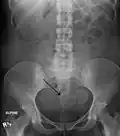

A very large (9 cm) fibroid of the uterus which is causing pelvic congestion syndrome as seen on CT -